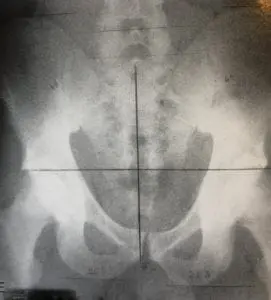

Cobbvinkel

Diagnos sätts efter röntgenundersökning där man kan se och mäta kurvaturerna och cobbvinkel. Cobbvinkel är sättet man mäter och klassificerar skolios. Över 10% behövs för diagnos.